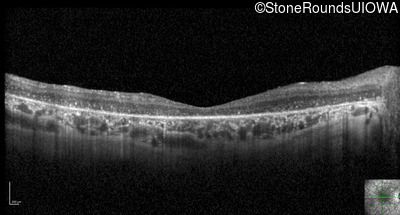

Optical Coherence Tomography - Right - 20/300 sc

Exemplar / OCT Stack

OCT Stack

Optical Coherence Tomography - Left - 20/300 sc